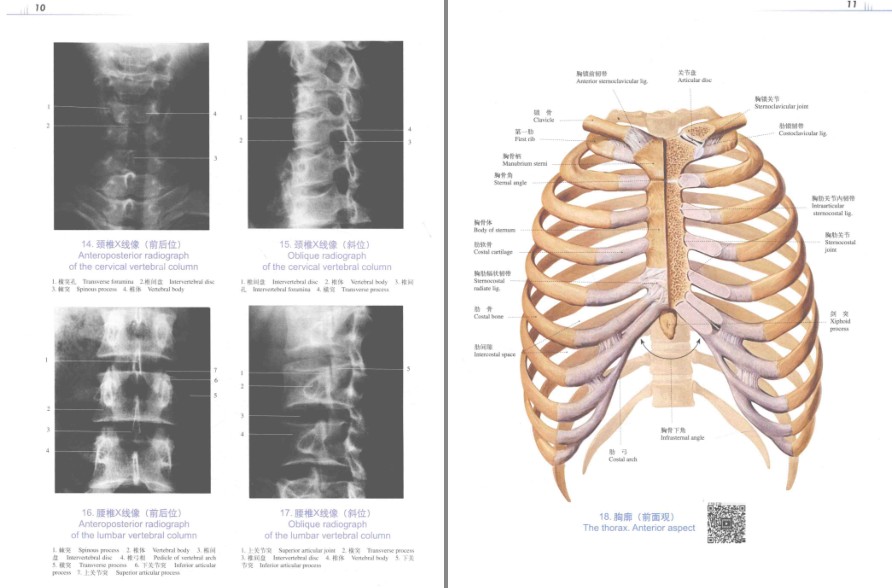

书名 《人体解剖彩色图谱》带你了解人体[pdf]

《人体解剖彩色图谱(第3版/配增值)》是我国第一部自编、手工绘制彩色图谱,以实物标本写生为主,色泽艳丽、结构清晰、边界明确、形态典型,极受读者欢迎。编排包括系统解剖和局部解剖两部分,系统解剖中的某些图采用“一图多用”的表现方法进行设计,使其得以在局部解剖图中予以综合展示。第3版图谱将以“提升品牌和质量”为目标,坚持“传承与创新结合、纸质与数字结合、传统技术与新兴技术融合、传统载体与新兴载体融合”为原则,进一步优化内容,同时通过二维码关联3D和AR等数字化内容,加强数字融合,实现纸质与数字的互动互补。并将根据最新版教材进一步完善体系,在前两版的基础上增加头部、躯干断层解剖等内容,最终实现系统解剖、局部解剖和断层解剖的完美融合!